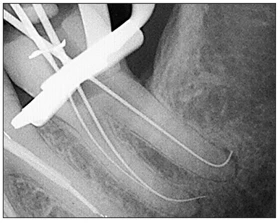

• Sử dụng một le số 10 để vượt qua các mảnh vụn gây tắc. Khi dụng cụ đạt tới chiều dài làm việc, nhẹ nhàng đưa đầu mút le tới và qua lỗ chóp một ít để thiết lập sự thông suốt (Hình 25-1).

Hình 25-1 Thiết lập sự thông suốt ở một răng cối lớn hàm dưới với các chân răng cong và bệnh lý quanh cuống.